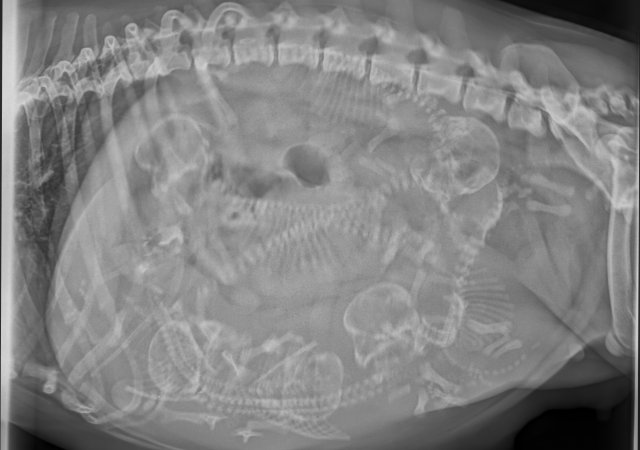

• Gebärmuttervereiterung (Pyometra)

• Eröffnung der Bauchhöhle (Explorative Laparotomie) zu diagnostischen Zwecken